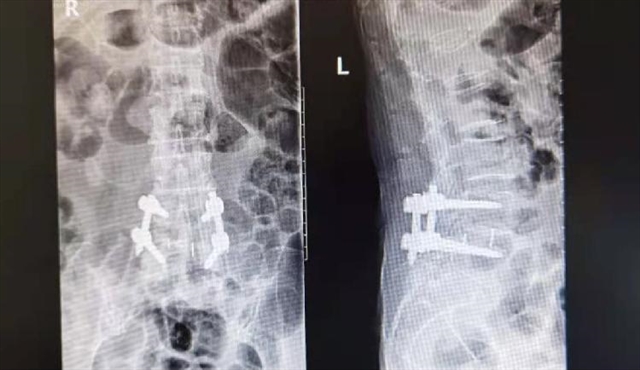

楚磊博士详细询问了林老师的病史,细心察看了她以往的病例和检查报告,完善了相关检查,核磁共振(MRI)显示L4/L5、L5/S1椎间盘突出,马尾神经受压明显。“除了手术,保守治疗无法使狭窄的椎管变得宽松,也就不能接触脊髓和神经根的压迫,若不及时治疗,病情很可能进一步恶化。”楚磊博士谈到,病人需要通过手术将部分椎间盘去除,再用椎间融合器来维持合适的椎间隙高度,并用骨移植促使相邻椎体的融合,间接减轻神经压迫,保持脊柱稳定。为了保证手术效果,同时最大程度减小病人的创伤,楚磊博士为林老师制定了最佳手术方案——腰椎侧方椎间融合术。

在与病人进行充分沟通后,手术在医院副院长、骨科学科技术带头人邓忠良教授,骨科脊柱外科中心副主任柯珍勇教授的指导下,由楚磊博士主刀进行。术中,楚磊博士每一步都精细入微地操作,通过微创管道,精准而小心地切除故障的椎间盘组织,安装椎间植骨融合器,将脱出于椎管的髓核取出,确保神经根无压迫,手术非常顺利,历时2小时,术中出血仅100ml。

“以腰椎管狭窄引发的病症为例,如果把椎间盘比作饱满的‘包子’,那么随着磨损、老化,它就逐渐变薄,压成‘饼子’,膨出的部位会造成椎管狭窄,压迫神经或脊髓,导致疼痛、麻木或腰肢无力等症状。”楚磊博士谈到,要解决椎管狭窄,就需要让“饼子”重新变回“包子”,对此,腰椎侧方椎间融合术主要通过5步实现:1.以侧入路植入扩张管道;2.植入自动撑开器;3.摘除椎间盘;4.植入大融合器;5.植入椎弓根螺钉。

那么,为什么说上述术式“更微创”呢?楚磊博士解释道,上面也提到了,腰椎侧方椎间融合术通过身体侧面的切口来显露脊柱,因此与PLIF、TLIF、MISTILF等腰椎融合术相比,该术式借助微创管道,经腹膜后间隙行腰椎间盘切除减压及椎间融合术,不需要侵犯椎管,不需要直接进入椎间孔及复位神经根,不需要剥离腰背部肌群,不需要破坏后方骨性结构,因此术中并不会导致硬膜粘连,也不会损伤神经根,最大限度保留了人体重要结构的完整性,具有创伤更小,术中出血相对更少,手术时间与术后康复时间更短的特点。

具体表现为:1.能放置更大的椎间融合器,使得椎间融合器与终板之间有更大的接触面积,这一结果最终会带来更好的稳定性、更低的沉降率、更优势的力学性能;2. 椎间盘融合器的接触面积增大后,可以放入更大体积的植骨材料,增强脊柱融合,稳定性好,后期椎间融合成功率更高;3. 以侧入路植入扩张管道,能起到间接减压的作用。